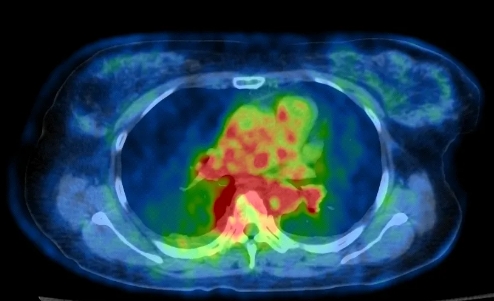

不负众望,PET/CT发现了新的线索——“右侧乳腺外上象限结节,代谢轻度增高”。正是这轻度的代谢增高,给医生提供了明确诊断的新思路,这是一例隐匿性乳腺癌伴肺、骨多发转移。最后病理证实是癌,免疫组化支持乳腺来源。

PET/CT提示“右侧乳腺外上象限结节,代谢轻度增高”